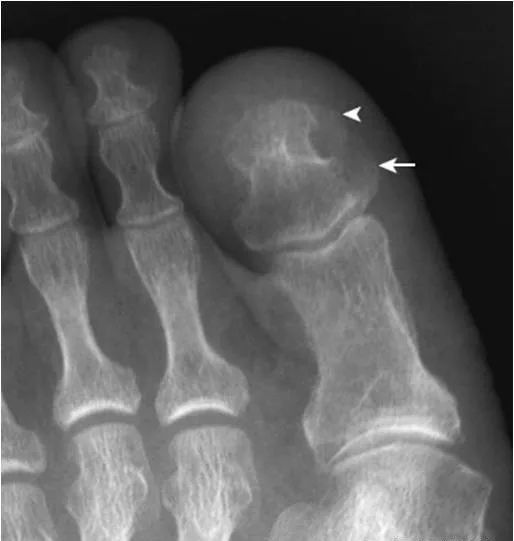

20.拇趾远节趾骨隆起:

成人拇趾远节趾骨内侧可见疣状突起(箭),为正常变异,并非外生骨疣。该例突起明显,与甲粗隆(箭头)形成骨桥,为一种特殊变异。

21.足趾副骨:

趾跖关节内侧见点状骨性灶(箭),又称关节旁骨,一般无病理意义,但有时可引起邻近骨生长障碍和坏死。要与撕脱骨折鉴别。